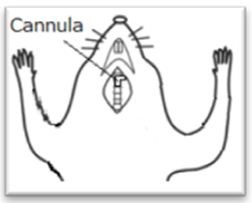

- Cannula was inserted by opening a direct airway through an incision in the trachea (see Figure1).

Figure 1. Cannula was inserted into a direct airway through an incision in the trachea after opening